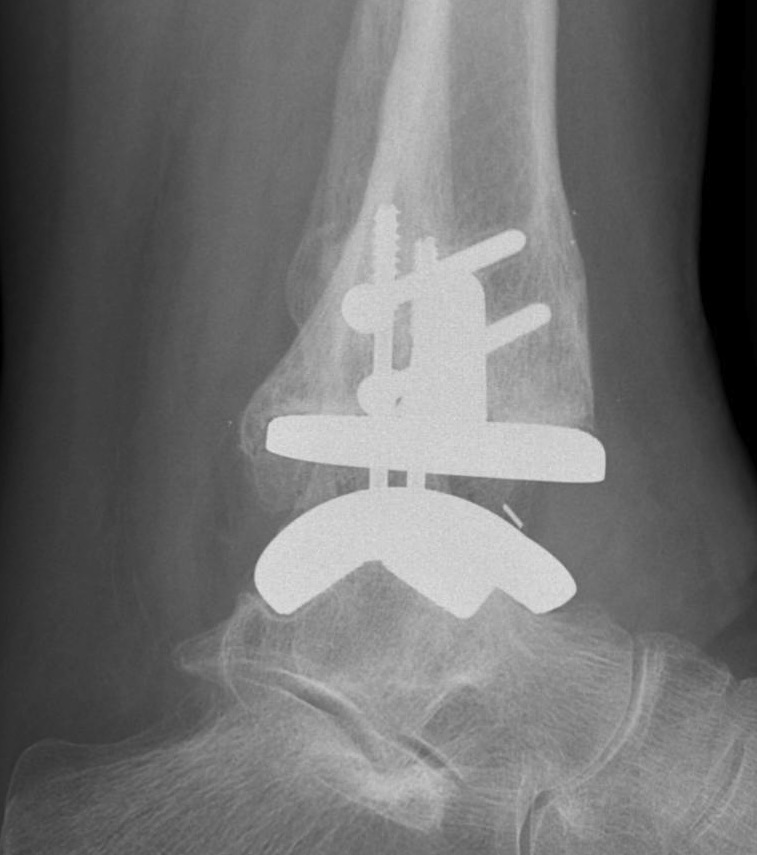

Infinity implant STAR implant Inbone

Agility Salto Tolaris Trabecular metal

A. Anterior approach

Tibial cut

- distal alignment jig / extramedullar jig +/- image intensifier +/- patient specific jigs

- resect few mm above eroded bone

- preserve medial and lateral malleolus

Talar dome resurfacing

- jig to make chamfer cuts

Insert mobile / fixed bearing